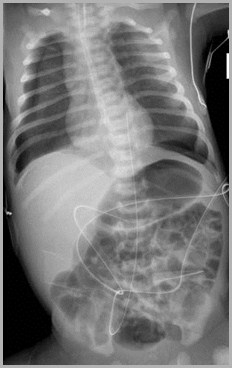

Umbilical Venous Catheter in Portal VeinUAC in iliac

Auckland